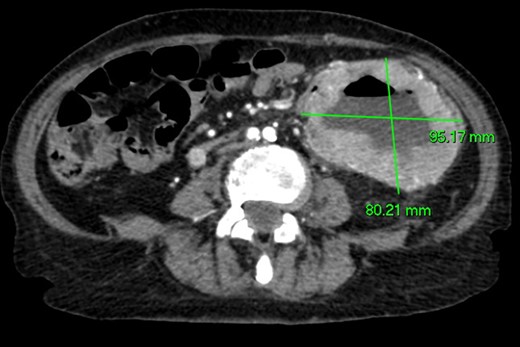

CT angiography (Figs 1 and 2)—large 9 cm exophytic cavitating lesion arising from jejunum with no evidence of active haemorrhage, with multiple further lesions in the duodenum. This was felt to be the source of the bleeding. Although the tumour was identified in this case by CT angiography, a simple contrast enhanced CT would almost certainly have demonstrated this tumour adequately, given the typical CT appearance of GIST, with significant contrast enhancement and heterogeneity.

Axial CT imaging. Large exophytic cavitating lesion arising from jejunum with no evidence of active haemorrhage.